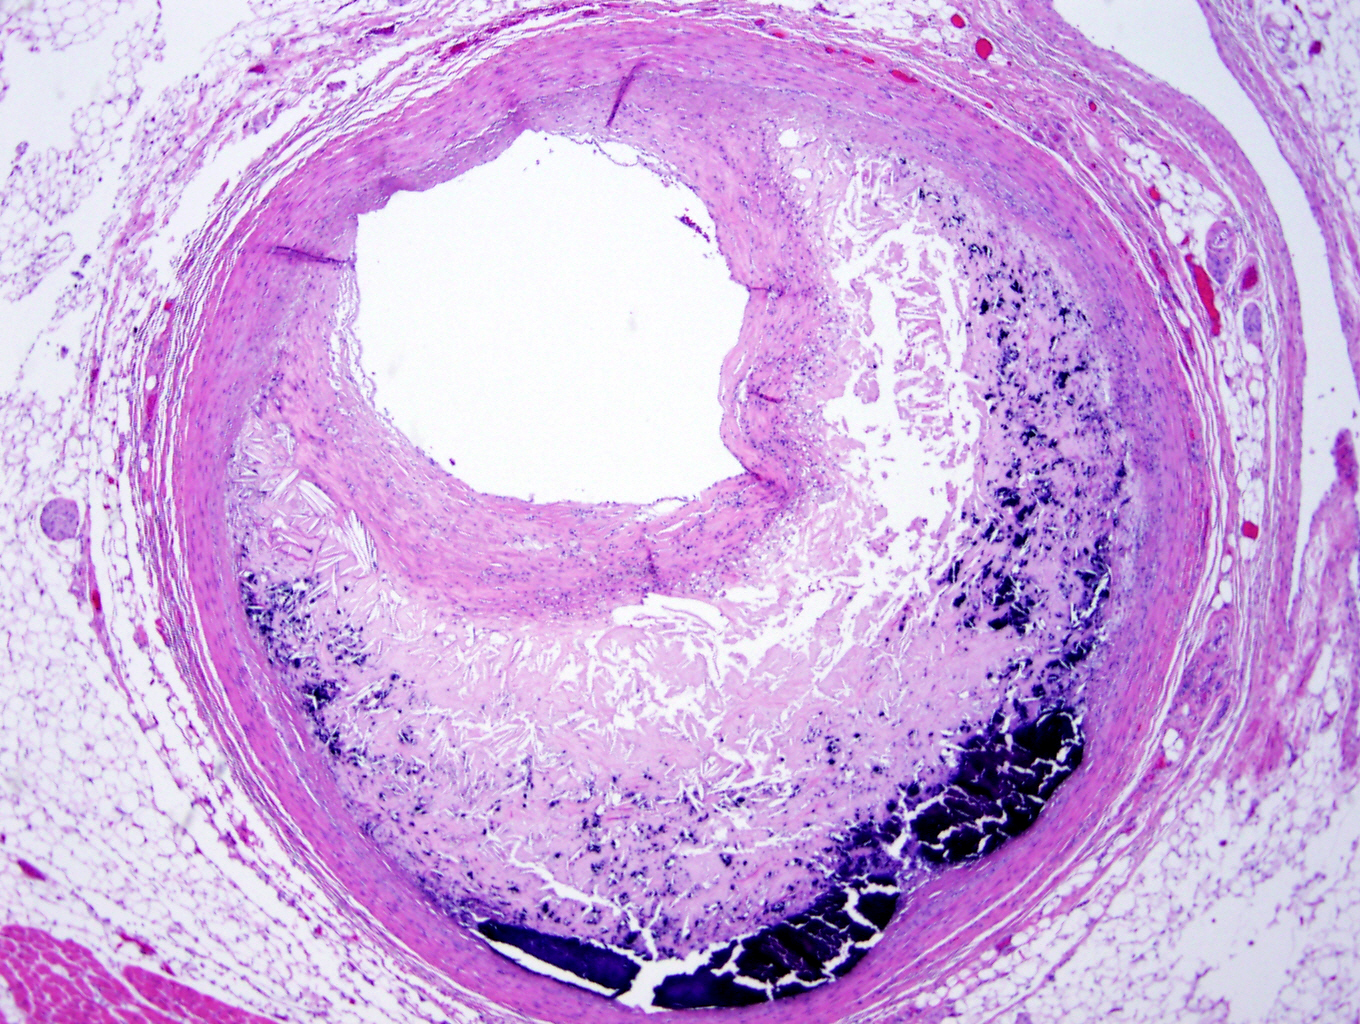

Microscopic (histologic) description

- Fatty streak: subendothelial accumulation of foam cells without necrotic core or fibrous cap

- Fibrous cap atheroma (Am J Med 2009;122:S3):

- Well formed necrotic core with overlying fibrous cap; smooth muscle cells, macrophages, lymphocytes and connective tissue components may be present

- With rupture: luminal thrombus communicates with underlying necrotic core

- With erosion: luminal thrombosis; no communication of thrombosis with necrotic core

- Fibrocalcific plaque: collagen rich plaque, contains large areas of calcification with few inflammatory cells, necrotic core may be present

Microscopic (histologic) images

Board review style question #1

A 75 year old man presents with acute chest pain, shortness of breath and EKG changes concerning for acute myocardial infarction. At autopsy, the above finding is identified when examining the coronary arteries. Which of the following is a risk factor for this finding?

- Coronary artery plaque with thick fibrous cap

- Lipid rich coronary artery plaque with thin fibrous cap

- Low blood triglyceride level

- Patient is a nonsmoker

Board review style answer #1

B. Lipid rich coronary artery plaque with thin fibrous cap